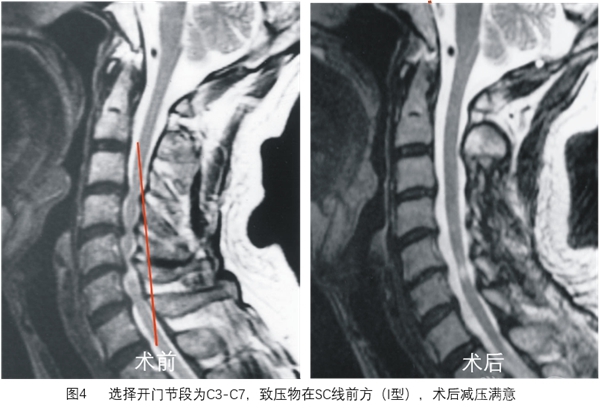

SC线同时反映颈椎管曲度、脊髓曲度与致压物的关系,根据SC线及其分型能更好地预测颈椎开门椎管成形术后脊髓减压的效果(图3~图8)。

选择开门节段后,划出SC线,分型为I型开门术后减压满意,II型大部分可获得减压,III型减压不满意。